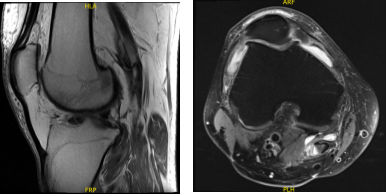

A 57-year-old patient was in our office with complaints regarding right knee pain. He tried physical therapy as well as anti- inflammatory medications, which did not help. He got an MRI done, which showed complex medial meniscus tear.

MRI Right Knee Non-contrast